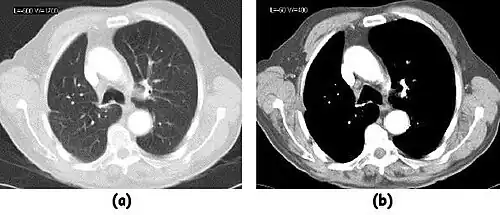

- Figure 7.15.3 illustrates the use of a relatively narrow window to highlight pathology in the lungs.